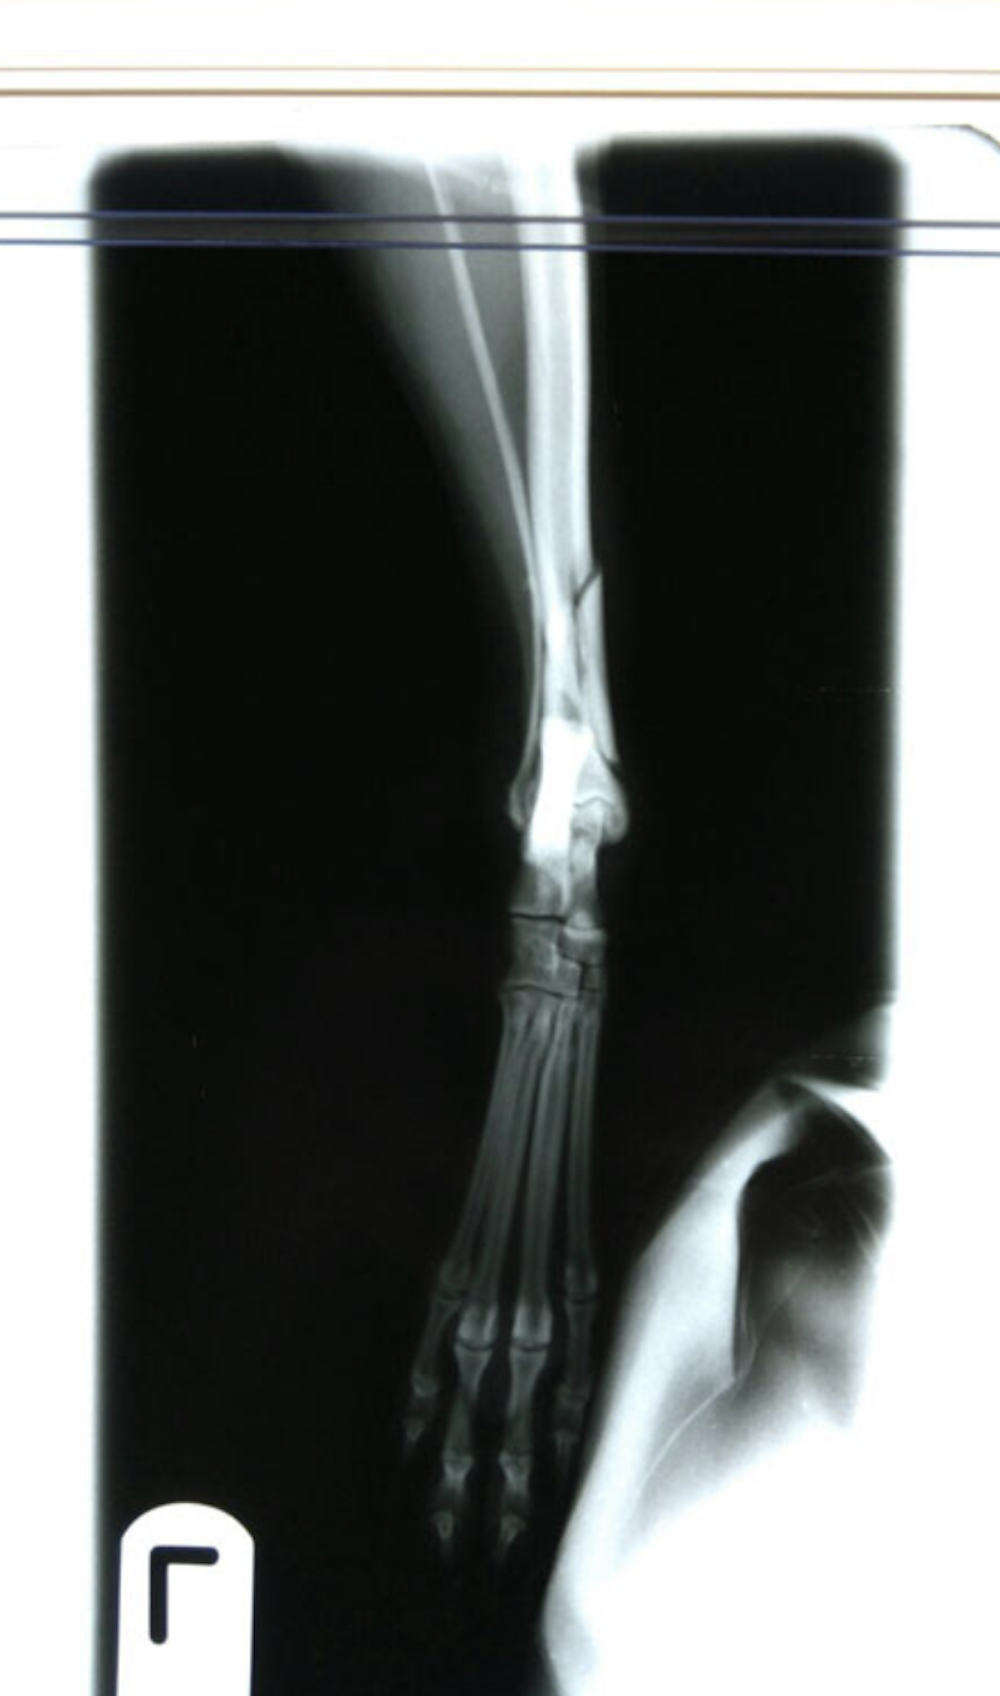

Radius and Ulna Fracture Repair

Example of Minimally Invasive Radius and Ulna Fracture Repair.